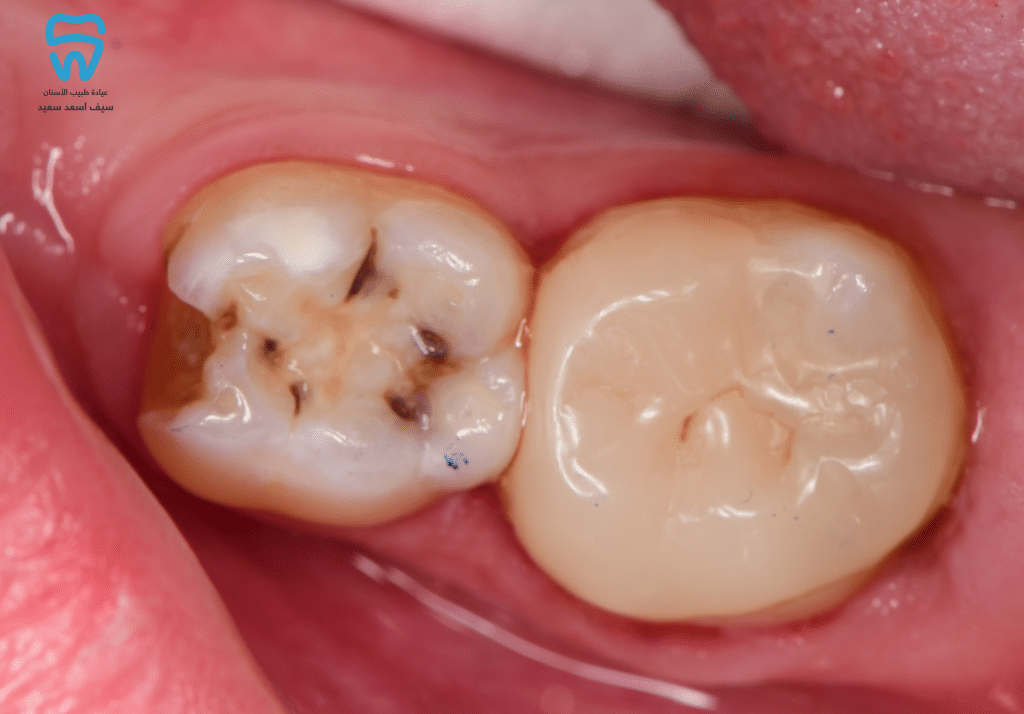

9-year-old female patient presented with pain during eating and discomfort in the lower right permanent molar.

Complete caries excavation with pulp amputation and cessation of haemorrhage.